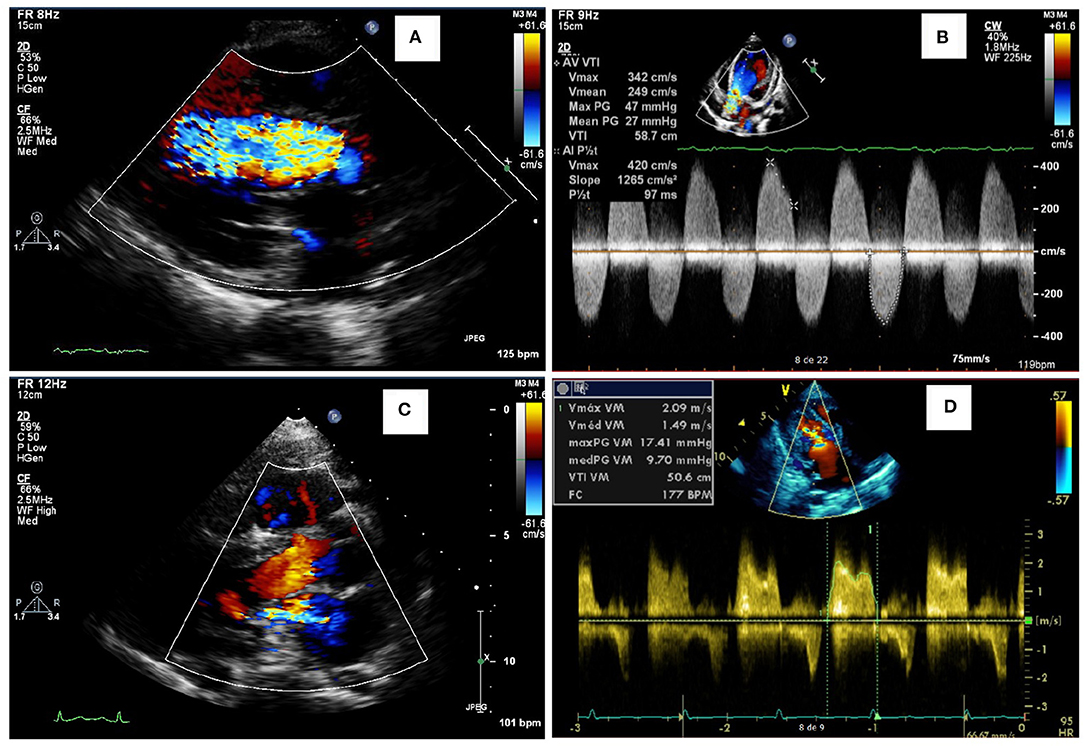

Among the 76 patients included in this study, left side valvular disease was a frequent finding, with mitral and aortic thickening being reported in most patients in all four MPS types (Figure 1). Furthermore, mitral and aortic insufficiency, mostly mild, were frequently found in patients with MPS I, II, and VI, but were also observed in a significant proportion of patients with MPS IVA. To a lesser extent, tricuspid valve thickening and insufficiency were also present in patients with MPS types I, II, and VI. Heart valve involvement was both more prevalent and more severe in adult patients (Figure 2; Table 3).

Figure 2. Representative abnormalities identified in the valves of the patients of this study. Aortic insufficiency (A) and aortic stenosis (B) in a female in the age range of 26–30 years with MPS IVA, who also had a reduced ejection fraction (35%). Mitral insufficiency (C) in a male in the age range of 21–25 years with MPS VI. Mitral stenosis (D) in an adolescent male with MPS II.